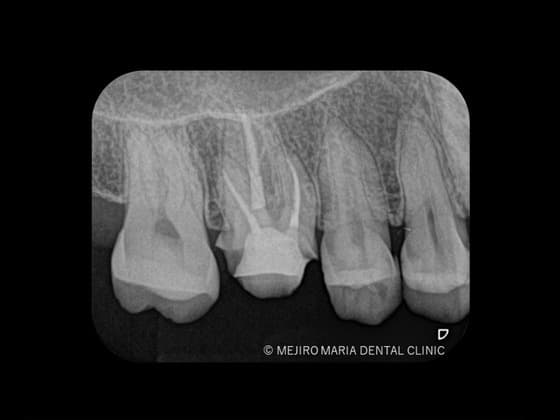

不可逆性歯髄炎の症例

| 主訴 | 3日前よりズキズキする痛みを感じ始め、初診当日は頭に突き抜ける痛みがある |

|---|---|

| 治療内容 | 根管治療(抜髄)|精密根管治療 |

| 治療期間 | 1週間 |

| 治療費用 | 154,000円(税込) |

| リスク・副作用 | 精密根管治療はすべて自費の治療になります。 根管治療終了後には術後性疼痛がある場合があります。 根管治療が予後不良の場合は歯根端切除術を行う必要があります。 |